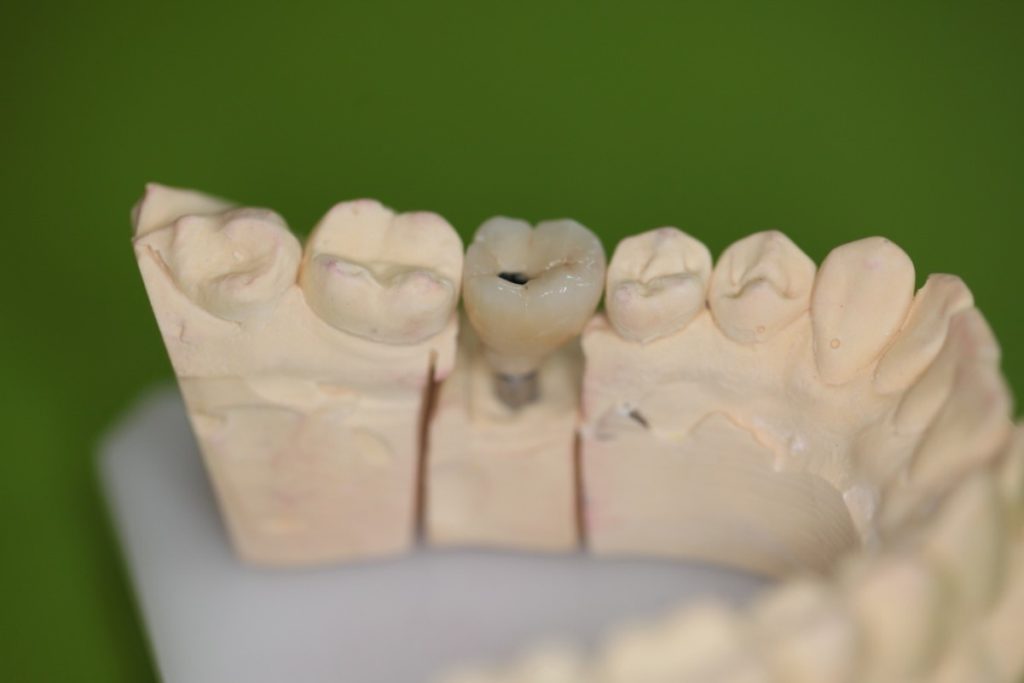

Side view of the screw-retained implant crown intended for the lower left first molar on a gypsum cast.

Upper view of the screw-retained implant crown intended for the lower right left molar on a gypsum cast.

Lingual side view of the screw-retained implant crown intended for the lower left first molar on a gypsum cast.